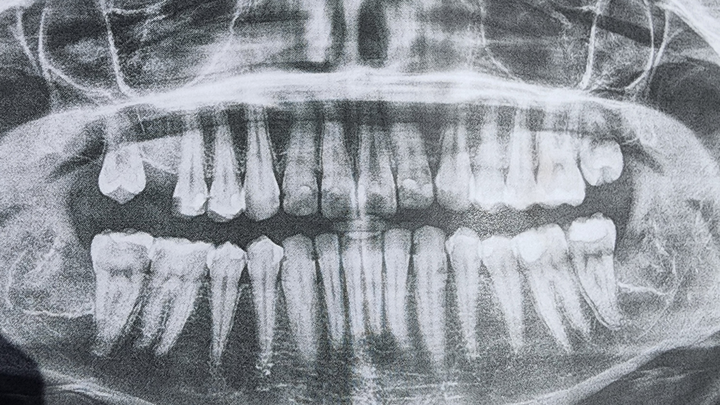

Hello. My name is Ash and those x-rays are of my not so good teeth. I knew that they weren't that good but they were worse than I could ever have imagined.

Due to an old dentist seemingly giving me bad fillings before leaving the practice, it seems I need 4 Crowns, 1 or 2 Root Canals, and a whole ton of fillings. I was prepared for a couple thousand but it seems they want about 12,400 in total. And this includes a dental plan card they let me sign up for to half the entire bill. They want me to pay before each appointment and at this point I dont know what I can do.